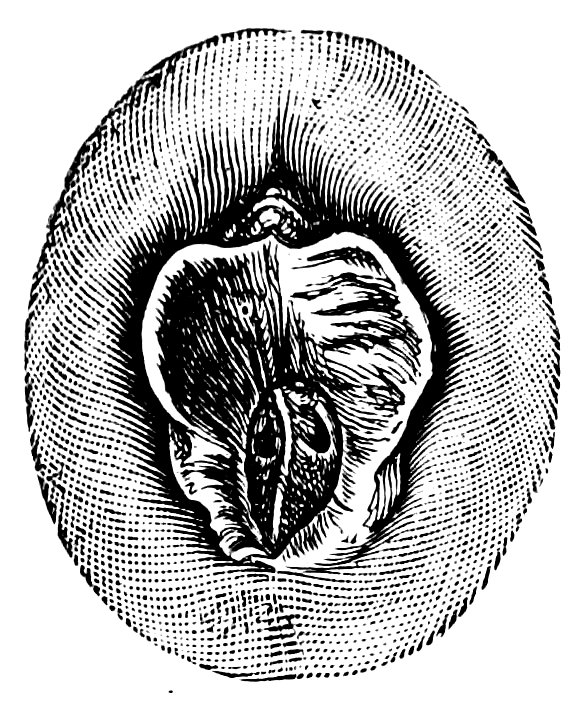

| 12. | Female external genital organs of a virgin | 54 |

| 13. | The external genital organs of a virgin | 55 |

| 18. | Annular Hymen | 64 |

| 19. | Annular Hymen | 64 |

| 20. | Semilunar Hymen | 65 |

| 21. | Annular Hymen with Congenital Symmetrical Indentations | 65 |

| 22. | Fimbriate Hymen | 65 |

| 23. | Deflorated Fimbriate Hymen | 65 |